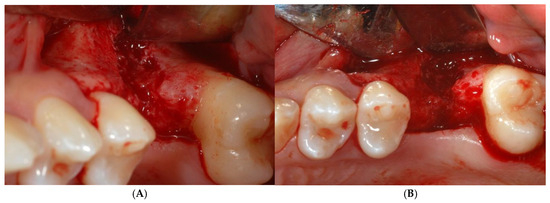

After making the crestal incision, two vertical buccal releasing incisions—mesial to the second premolar and distal to the second molar—were performed. Then, a mucoperiosteal flap was raised, revealing the wide ridge deficiency (approximately 5, 7, and 9 mm in the mesio-distal, bucco-palatal, and corono-apical directions, respectively), highlighting the impossibility of achieving proper implant stability (Figure 3A,B). Then, a copious bleeding recipient site was created by bur perforations through the medullary spaces. A TR-dPTFE membrane (Cytoplast® Ti 250 Buccal, Osteogenics Biomedical, Lubbock, TX, USA) was shaped and trimmed with scissors to fit the ridge defect (Figure 4A), taking care to position the membrane edges 1.5 mm away from the adjacent roots, and stabilized with two pins on the buccal side. A graft of 100% NH embedded in a silica gel matrix (NanoBone® Artoss, Rostock, Germany), in the form of 0.6 × 2 mm granules, wetted with sterile saline (Figure 4B), was applied and compacted with a spoon/plugger tool to avoid leaving voids, but without over-compacting the material (Figure 4C). The membrane was moved to the palatal side and stabilized with an additional pin to the palatal bone wall (Figure 4D,E). A continuous periosteal incision along the entire length allowed the buccal flap to move coronally, followed by tension-free suturing using horizontal mattress and single stitches (Figure 5A) with PTFE material (Cytoplast® suture, Osteogenics Biomedical, Lubbock, TX, USA), which were removed 14 days later (Figure 5B). Healing was uneventful, and after a period of 10 months (Figure 6A–C), the site was re-opened for membrane removal and implant insertion. A smaller paramarginal trapezoidal mucoperiosteal flap, sparing the periodontum of the adjacent teeth, was raised (Figure 6D,E). The membrane was easily removed, and the defect appeared to be completely regenerated (Figure 6F). A 4 mm wide trephine bur (Stoma®, Emmingen-Liptingen, Germany) was used to harvest a bone biopsy (Figure 7A), measuring 3 mm in diameter and about 6 mm in length (Figure 7B), so as not to extend the future implant bed preparation. The implant bed was then definitively prepared with the drill dedicated to the chosen implant (Figure 7C), a 5.0 × 9 mm implant (Camlog® Screw Line Promote Plus Biotechnologies, Basel, Suisse). The bone biopsy was immediately fixed in 10% neutral buffered formalin and stored at room temperature. The specimen was then decalcified in formic acid, dehydrated in progressively more concentrated ethanol, and finally embedded in paraffin. Sections of 5–6 µm thickness were cut with a microtome (Leica SM 2.400, Solms, Germany) and stained with hematoxylin and eosin and the Azan–Mallory staining technique for light microscopy. Histological evaluation and photo documentation were performed using the Axiophot microscope (Zeiss, Göttingen, Germany) at 12.5×, 25×, 100×, 200×, 400× magnifications.

Figure 7.

Trephine bur was used to harvest bone biopsy (A), measuring 3 mm in diameter and about 6 mm in length (B), during implant bed preparation (C). After implant insertion (D), a healing abutment was immediately connected (E) for transmucosal healing, avoiding additional surgery. Healing was uneventful and 2 months later (F), site was ready for prosthetic rehabilitation.

After implant insertion (Figure 7D), a healing abutment was immediately connected (Figure 7E) for transmucosal healing, avoiding additional surgery. After a 2-month healing time (Figure 7F), a provisional restoration was applied for progressive loading. At 6 months after implant insertion, a definitive porcelain-fused-to-metal crown was cemented (Figure 8A–C).